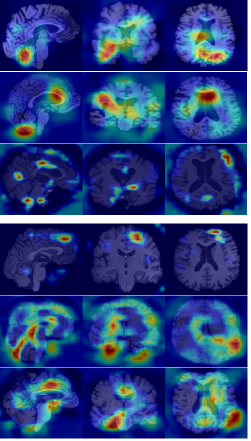

Refer to caption

(a)

(b)

(c)

Figure 6: Grad-CAM visualizations on MRI scans from ADNI and AIBL datasets. (a) Input images for NC, MCI, and AD groups. (b) Attention maps from the model without morphological modules. (c) Attention maps with morphological modules, showing improved focus on disease-relevant regions.

From a qualitative standpoint, Fig. 6 further presents Grad-CAM visualizations comparing the baseline 3D U-Net model and the proposed pseudo-morphological modules for AD detection. The leftmost column shows original MRI slices from both ADNI and AIBL datasets across three classes: NC, MCI, AD. The middle column illustrates attention maps generated by the baseline U-Net3D model, which are less focused, suggesting limited class-specific feature localization. In contrast, the rightmost column shows Grad-CAM results from the model enhanced with pseudo-morphological modules. These attention maps are more focused on areas in the brain which are known to be affected by AD, such as the hippocampus and surrounding medial temporal lobe. This indicates that incorporating class-specific morphological augmentations helps the model learn more discriminative and generalizable features for AD detection.